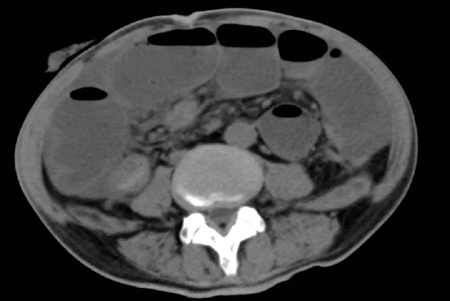

2022年5月的一个凌晨,一位93岁的老奶奶因为腹胀伴呕吐被送到了新龙泽院区急诊科,经过问诊和初步查体后,接诊医生考虑患者存在肠梗阻,立即为患者申请了急诊腹部CT检查,结果显示患者的升结肠存在一个巨大的肿物堵塞了肠腔。在给予补液和胃肠减压的同时,普外科立即对患者的病情进行了紧急评估和讨论。肿瘤导致患者出现肠梗阻,手术是唯一的解决方案,但患者高龄且身体非常瘦弱,围手术期发生肺部感染、心脑血管事件等并发症的概率非常高。普外科高鹏骥主任医师制定了急诊实施腹腔镜下右半结肠切除的手术方案,并在麻醉科和手术室医护团队的密切配合下顺利完成了手术。